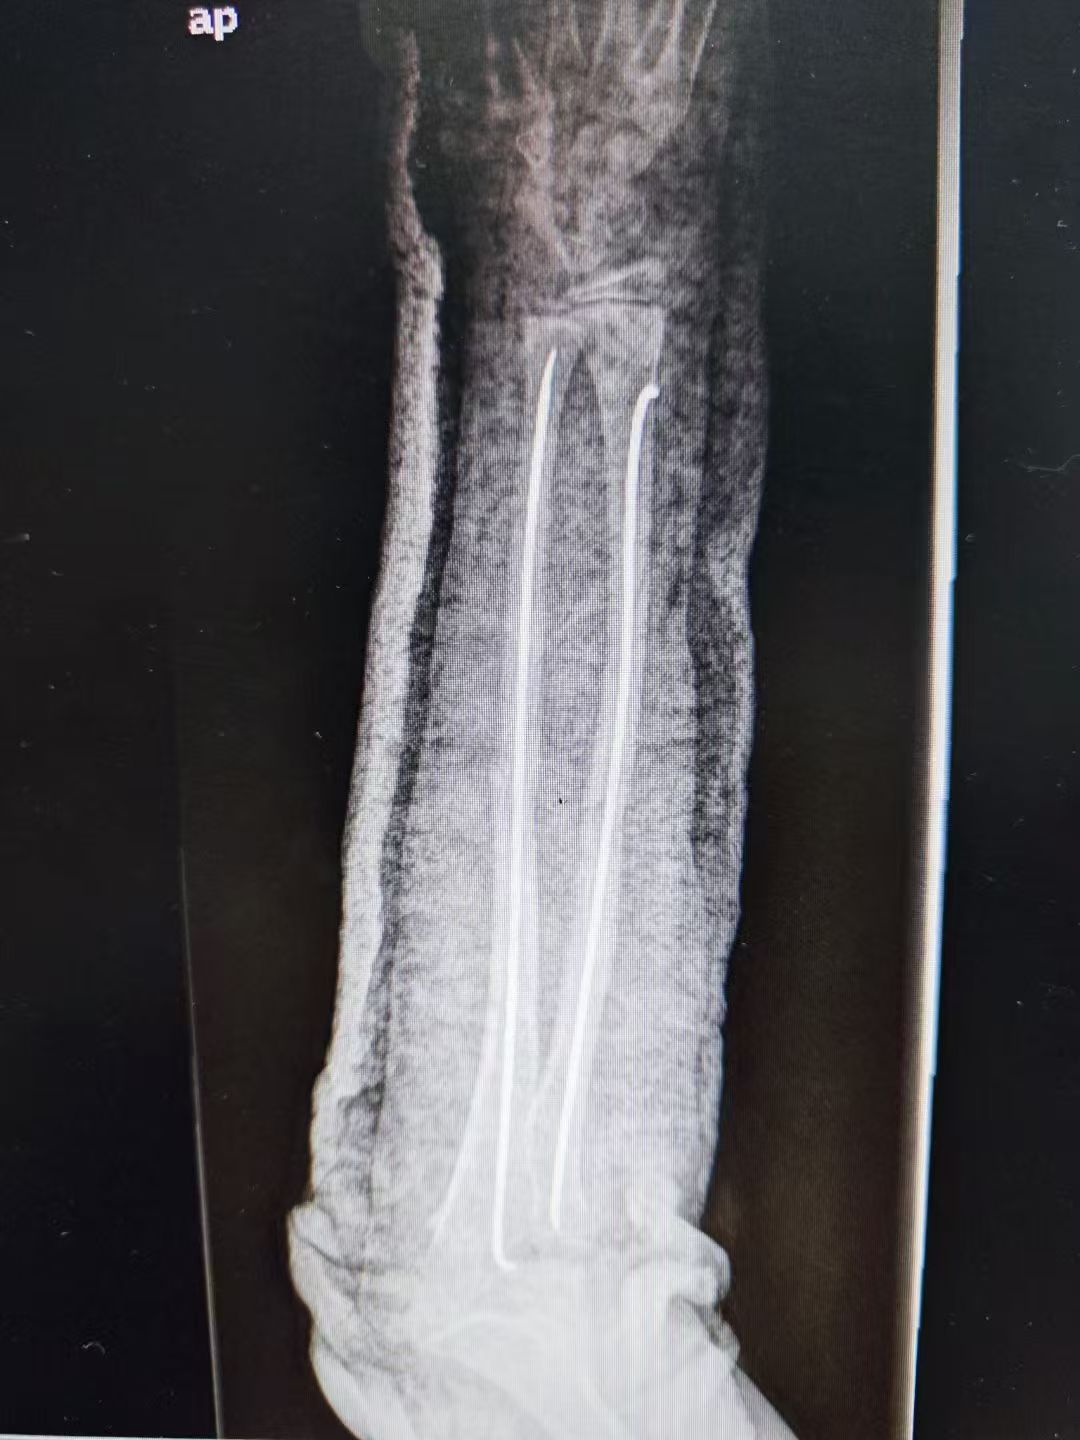

图片图片图片

儿童尺桡骨双骨折闭合复位微创弹性髓内针内固定